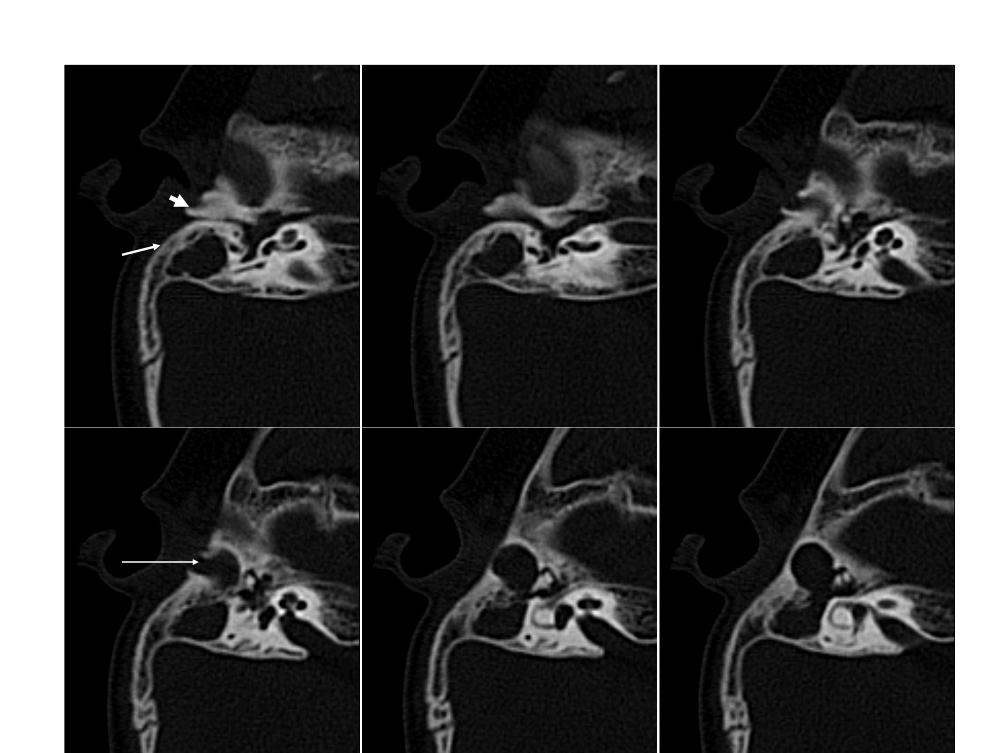

怎么回事?胡先生来到贵阳铭仁耳鼻喉医院检查,通过检查发现胡先生左侧外耳道、鼓室、鼓窦及乳突气房内充满大量密度增高影,左侧听小骨正常存在,鼓室未见明显增大,耳道里有大量脓性分泌物。原来胡先生患了左侧外耳道闭锁,需要通过手术来恢复。

耳道闭锁是指外耳道充盈的软组织或骨组织,可分为先天性外耳道闭锁和外伤性外耳道闭锁。

外耳道外伤闭锁,有局部创伤或手术史,外耳道有瘢痕形成,外耳道封闭,乳突ct检查可明确界定外耳道封闭、鼓室、乳突病变的范围。